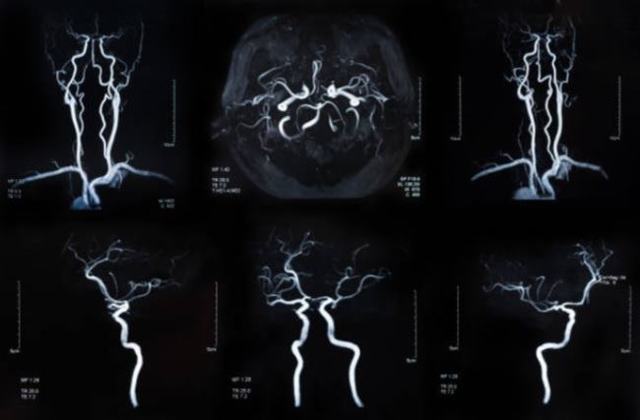

Диагностика аневризмы также включает ангиографию – рентгенологический метод, который проводится в комплексе с применением контрастных веществ.

Благодаря проведению этого исследования можно определить степень сужения того или иного сосуда, выявить расширение сосудов головного мозга, локализацию его разрушения.

Также в спектр диагностических возможностей ангиографии входит выявления слабых мест, то есть аневризм сосудов.

Полученные снимки обследований позволяют оценить состояние кровеносных сосудов и анатомических структур головного мозга в двух проекциях.

Проведение магнитно-резонансной томографии дает специалисту возможность оценить состояние сосудов и головного мозга в послойных срезах.

Благодаря мощному воздействию радиоволн и магнитного поля на послойных срезах четко визуализируются все структуры черепной коробки.

Трехмерное сечение состояния кровеносных сосудов и анатомических образований черепной коробки позволяет поставить точный диагноз.

- ангиография – рентген с контрастом, позволяет увидеть на снимке головной мозг полностью, и тем самым рассмотреть, где локализуется образование;

- КТ-ангиография – совмещение двух вышеуказанных методов;

- МРТ головного мозга – показывает более точную картину сосудов;

Аневризма сосудов головного мозга при проведении КТ-ангиографии